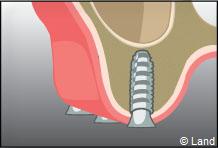

LES GREFFES D’APPOSITION

Elles sont indiquées dans les insuffisances d’épaisseur.

Les différentes étapes :

Prélèvement du greffon au niveau du site donneur

Apposition et stabilisation du greffon.

Recouvrement du greffon avec de l’os synthétique et une membrane

Après 6 mois de cicatrisation, il est possible de poser les implants qui recevront dans un deuxième temps les couronnes.

Apposition et stabilisation du greffon.

Recouvrement du greffon avec de l’os synthétique et une membrane